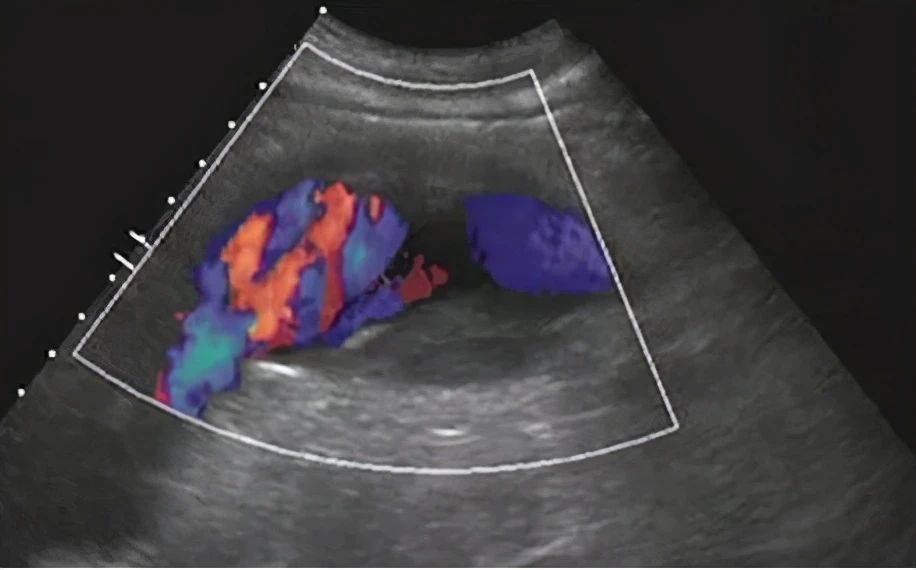

假性动脉瘤:通常发生在感染或血管损伤的患者中 , 由于血管腔破裂和血液流出 , 主动脉的三层结构不完整 , 主动脉破裂周围有组织 , 假性动脉瘤是比较危险的 , 它的瘤壁不是血管的结构 , 而是纤维素对血液的包裹 , 瘤腔内容物多为凝血块及机化物 , 但瘤腔仍与原动脉管腔相通 ,所以动脉瘤是比较脆弱的 , 很容易破裂导致大出血 , 使患者失血性休克 , 如果得不到及时有效的治疗 , 将会危及病人的生命。

【夹层|真性动脉瘤、假性动脉瘤、夹层动脉瘤特点及表现】股动脉穿刺介入治疗后 , 股浅动脉管壁连续性中断 , 可见撕裂口有血流喷射 。 该病灶内探及动脉样频谱 , 超声提示:外伤后假性动脉瘤形成 。